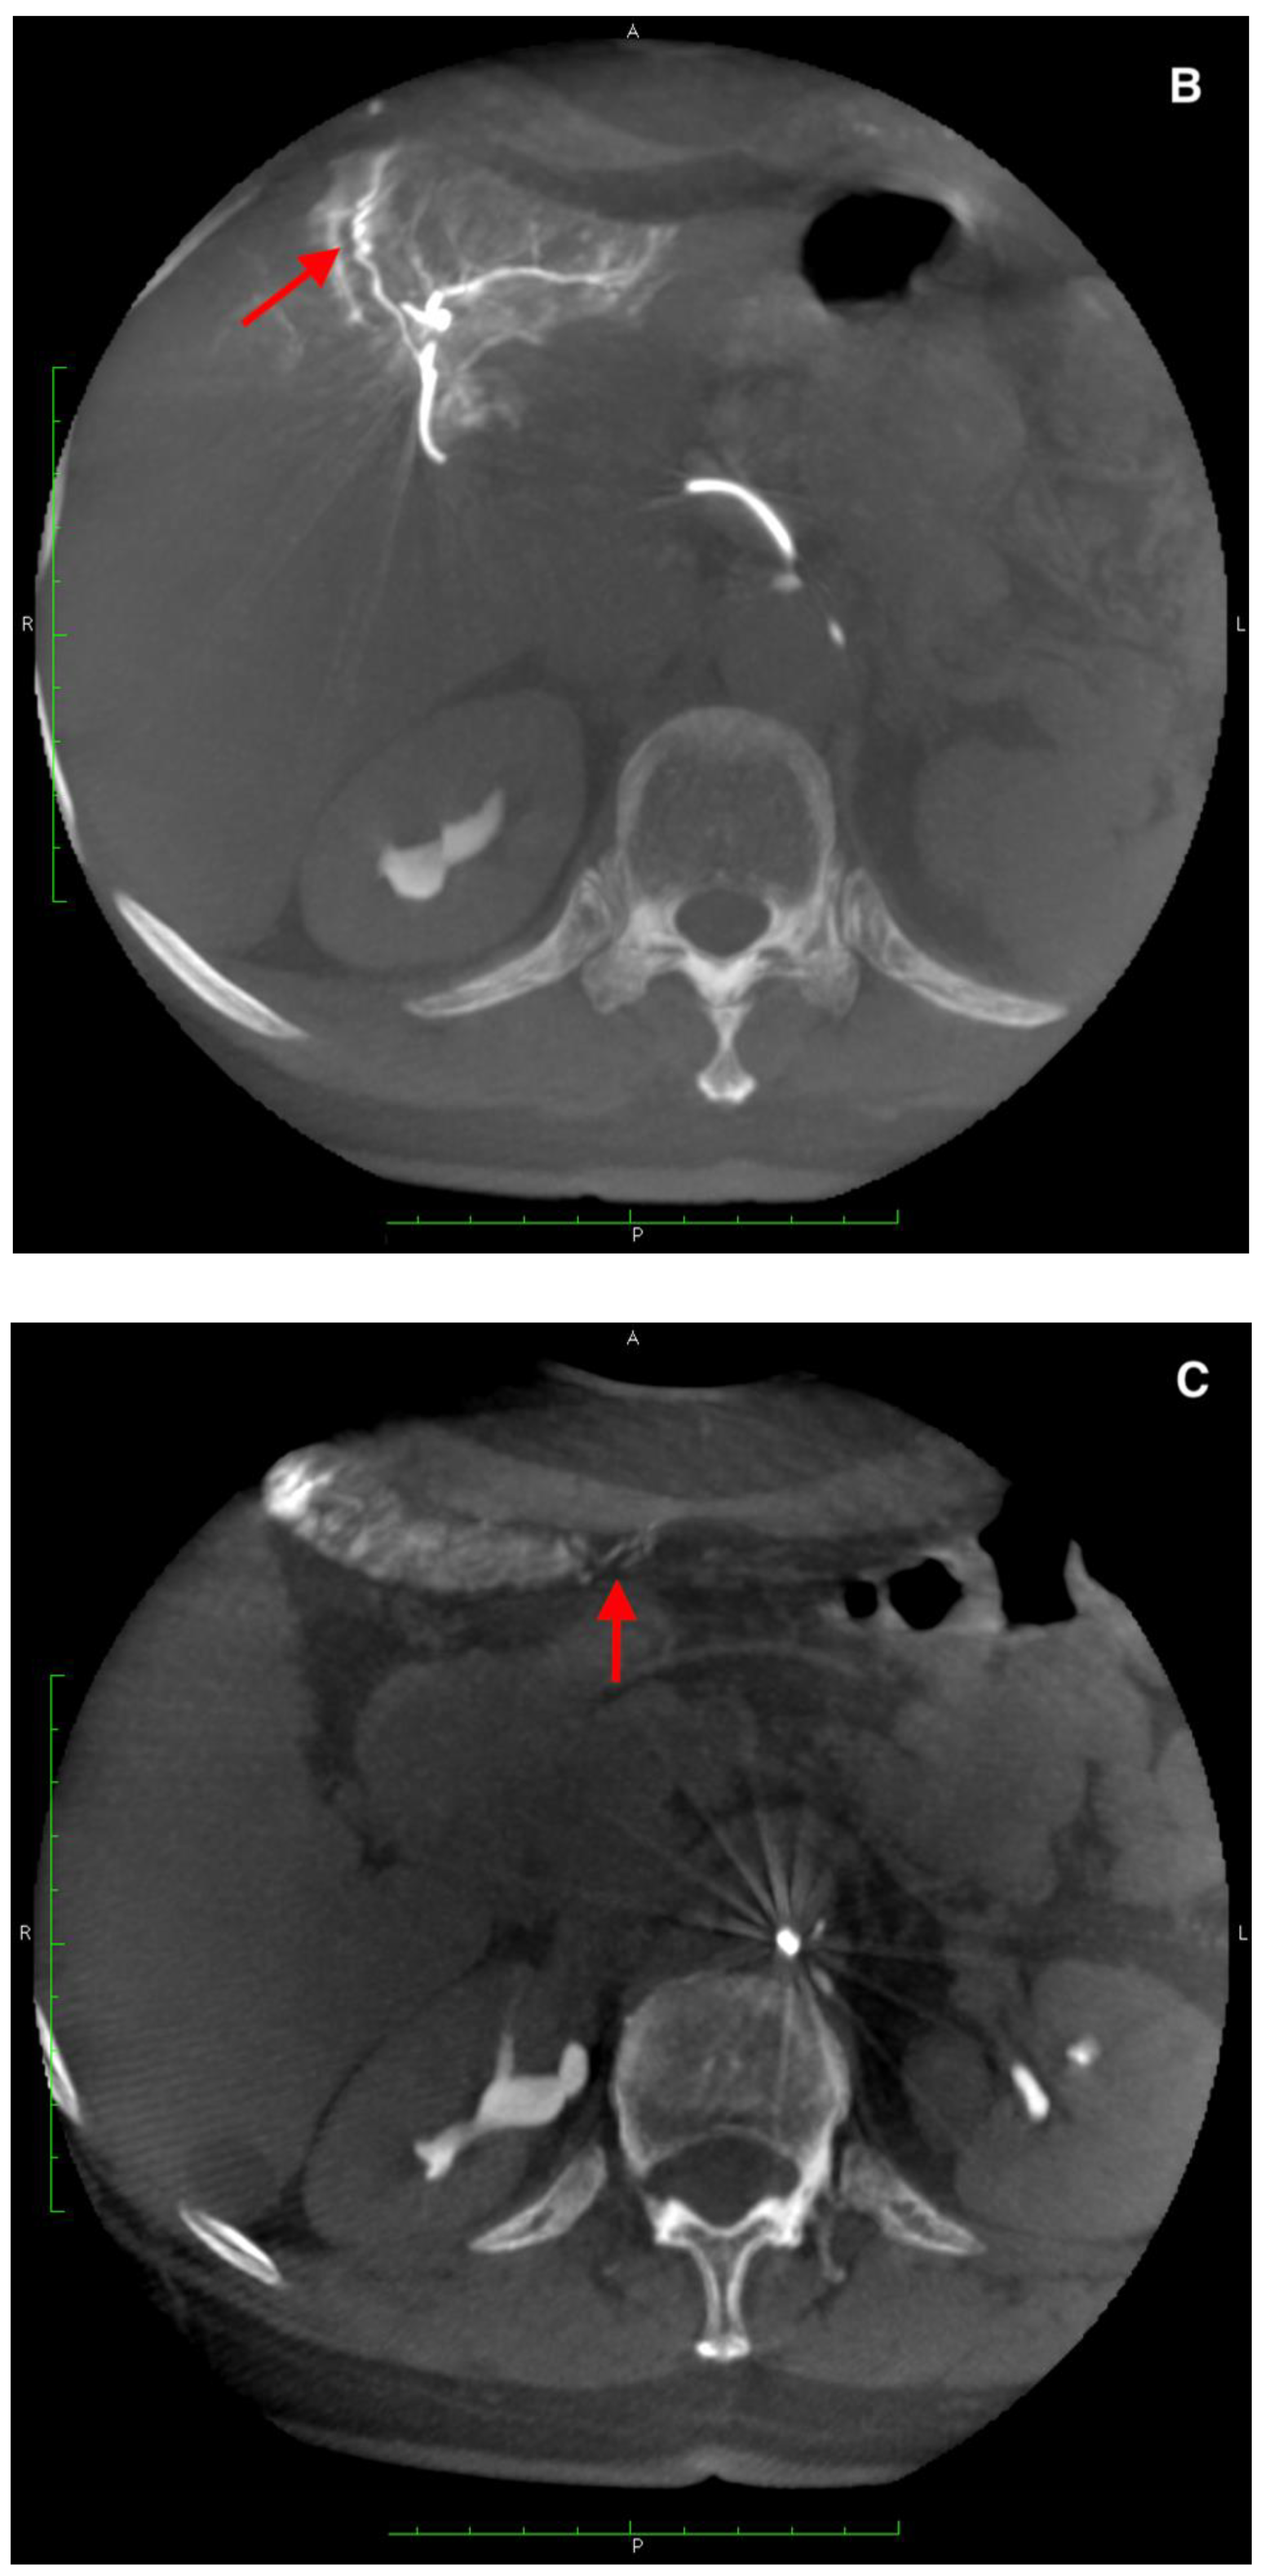

Figure 6.

(A) Angiogram of the left hepatic artery showing falciform artery travelling medially beyond the margin of the liver. (B) Its presence was confirmed on Dyna-CT and showed contrast enhancement of the abdominal wall (arrows) (C), and on SPECT/CT after 99mTc-MAA injection (D) (crosshairs).